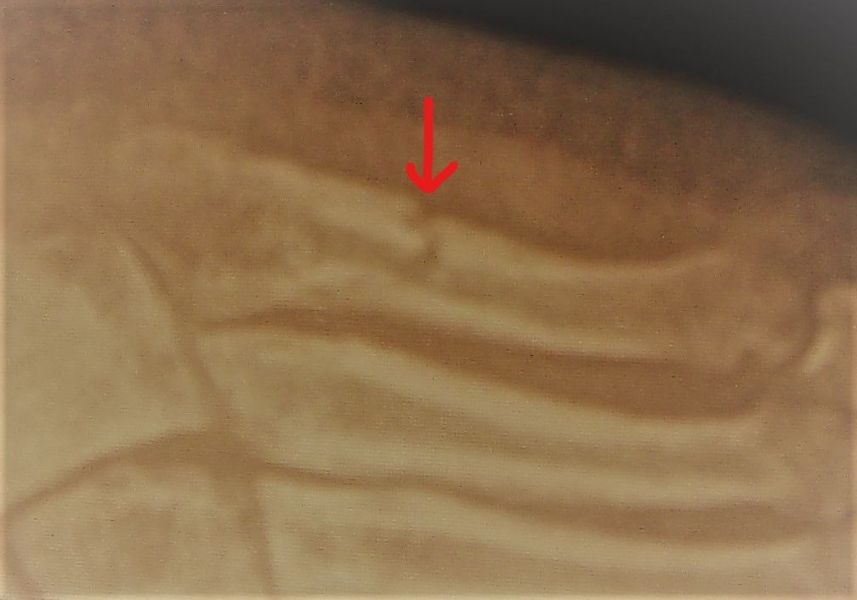

2. Atrophic nonunion 5th metatarsal (Jones fracture) of the left foot in a 25-year-old male.

Treatment: Percutaneous fixation with a screw and using specific grafts

I. Before surgery, anteroposterior x-ray of the foot II. Four months post-surgery with union of the fracture and patient is walking without pain.